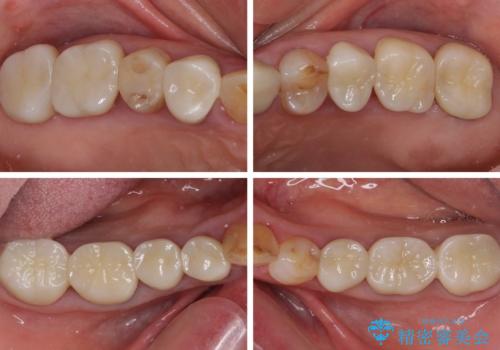

全ての奥歯の銀歯をセラミックに メタルフリー治療

途中体調を崩されてしまい、その間に仮歯が外れてしまうなど、治療期間が長引いてしまいました。

治療期間はかかってしまいましたが、念願のメタルフリーとなり、患者様には大変満足していただきました。